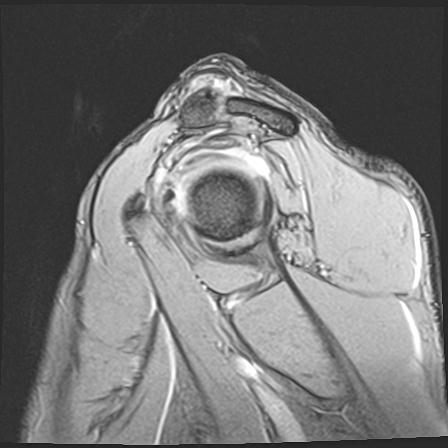

60058 3/9 11/4 右肩 2R+MRI 73歳男性 肩腱板損傷